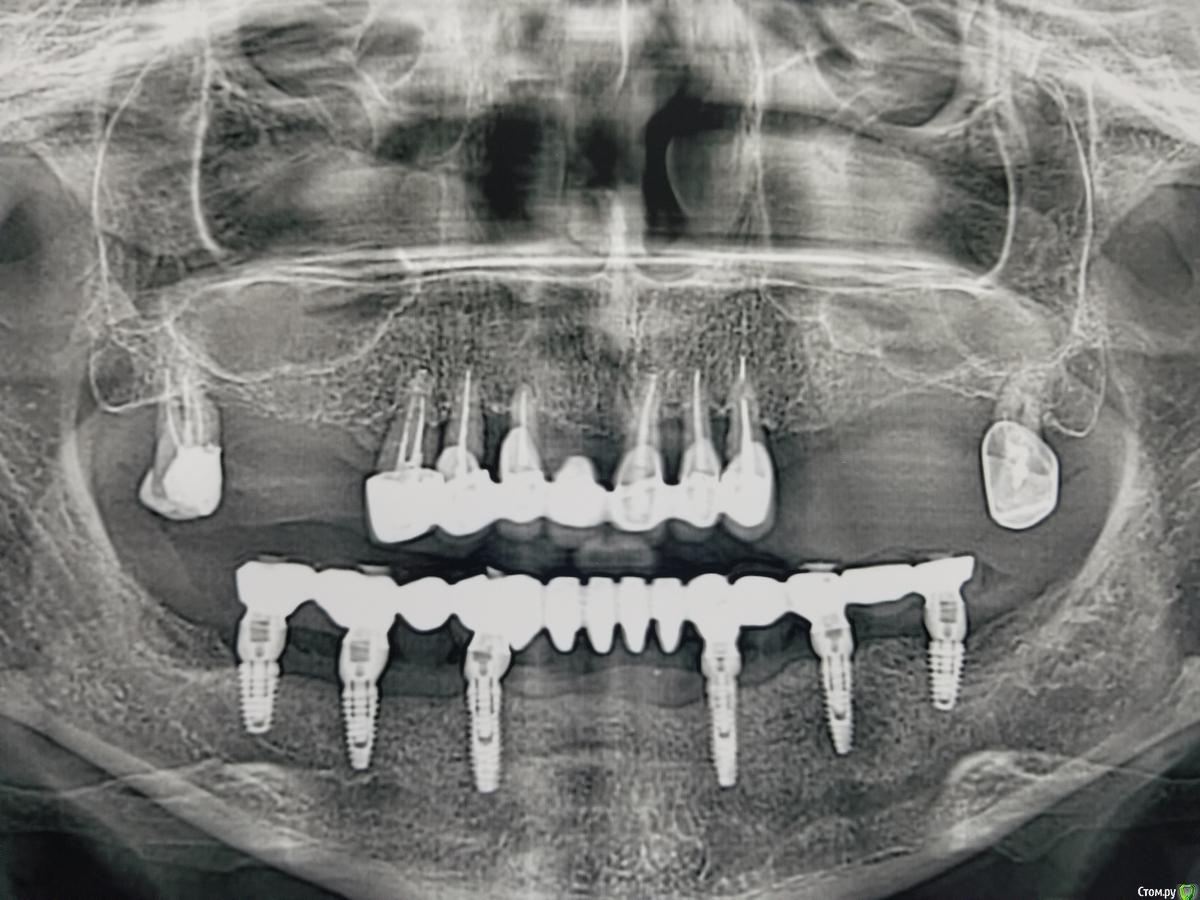

Kostoprav Опубликовано 14 июня, 2019 Поделиться Опубликовано 14 июня, 2019 Ксено+ауто +i prf, поверх титановых мембран перикард. кт через 5 мес.при и создании прикрепленки использовалась свиная дерма отечественного производителя 4 Ссылка на комментарий

Ethan Hunt Опубликовано 17 июня, 2019 Поделиться Опубликовано 17 июня, 2019 а когда стало можно все имплантаты внизу в таком виде объединять? Это же не верх и гуляет челюсть больше намного 1 Ссылка на комментарий

vgraev Опубликовано 20 июня, 2019 Поделиться Опубликовано 20 июня, 2019 спасибо за клинический случай! скажите,пожалуйста, это сетки,фиксированные заглушками, или смарт билдеры со спейсерами? Ссылка на комментарий

АнтонТЛТ Опубликовано 20 июня, 2019 Поделиться Опубликовано 20 июня, 2019 Ничего не обречено на провал)Верхняя челюсть состоит из двух частей, которые между собой двигаются. Поэтому не рекомендуется связывать в одну конструкцию правую и левую сторону. Карл Миш конечно крутой чувак, но некоторые данные в его книге уже устарели. 3 Ссылка на комментарий

L.E.S.I.K. Опубликовано 21 июня, 2019 Поделиться Опубликовано 21 июня, 2019 Миш не рекомендует объединять 4 импланта на полностью беззубой челюсти- если 2 установлены кпереди от ментальных отверстий и по одному дистально от ментальных на каждой стороне, мотивирую это скручиванием челюсти во время функции. 1 Ссылка на комментарий

Kostoprav Опубликовано 28 июня, 2019 Автор Поделиться Опубликовано 28 июня, 2019 спасибо за клинический случай! скажите,пожалуйста, это сетки,фиксированные заглушками, или смарт билдеры со спейсерами?сетки фиксировал спейсерами Ссылка на комментарий

Bier Опубликовано 28 июня, 2019 Поделиться Опубликовано 28 июня, 2019 Вы что на доктора напали? Нижняя челюсть изгибается во время открывания и закрывания рта, и процесса жевания. и действительно ряд авторов не рекомендует соединять имплантаты стоящие по разные стороны от ментального отверстия.И большое количество авторов вообще при протезировании полных дуг н.челюсти не устанавливают имплантаты дистальнее ментальных отверстий.Тем не менее и объединенные конструкции существуют. С большими сроками наблюдений их показывал Арам Давидян. 1 Ссылка на комментарий